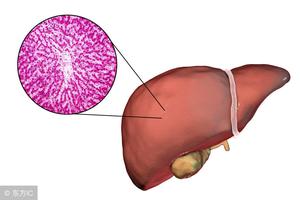

不少人B超、CT提示有“肝内钙化灶”,到底是什么意思?一文说清

肝钙化灶推荐内容: 第一反应可能觉得是不是和“钙”有关系? 其实不然。我们用通俗的语言解读就是“肝脏曾经有过损伤”,现在已经结痂好了,只是结的痂还没有掉罢了,在影像上可表现为肝内...

肝钙化灶推荐内容: 肝脏钙化灶一般可以通过B超或者是CT图像检查,检查的时候会发现肝脏上有一些像结石一样的东西或者是有高密度影像情况。肝脏钙化灶一般发生在20岁到50岁之间的人群会比较...

肝钙化灶推荐内容: 肝内钙化灶其实是钙的沉积所引起的一些影像学的表现,在B超上类似结石样的强回声,在CT上类似结石样的高密度影。以中青年人为主,一般为单个钙化灶,右肝多于左肝。

肝钙化灶推荐内容: 肝脏钙化灶是指在B超检查这个过程中,最终结果方面的显示上,肝脏部位有类似于结石一样的强回声,或是高密度影像的异常现象。通常在出现肝脏钙化灶时,肝脏内部并不会存...

肝钙化灶推荐内容: 肝脏钙化灶在肝病患者中检出率较高,这可能与先天发育、钙磷代谢紊乱等因素有关,也可能是肝脏创伤愈合过程中组织纤维化而形成瘢痕。